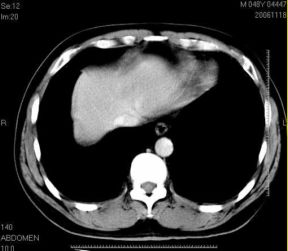

男性,48岁

肝内占位,性质?

肝内多发低密度占位病变,边缘清晰,无强化,肝转移瘤可能

肝内多发低密度占位病变,边缘清晰,无强化,肝转移瘤可能大,请将胃喝水充盈以后再扫描看看,我看大弯侧胃壁较厚。

肝内多发不规则形状低密度灶,强化不明显,考虑转移,积极查找原发灶

肝内多发低密度类圆形病灶,边缘清晰.增强无强化.

意见:1,考虑多发转移瘤;

2,囊肿与血管瘤不排除.

1肝内多发低密度影,考虑:转移瘤 2胃大弯侧胃壁明显增厚,建议胃镜检查除外胃癌